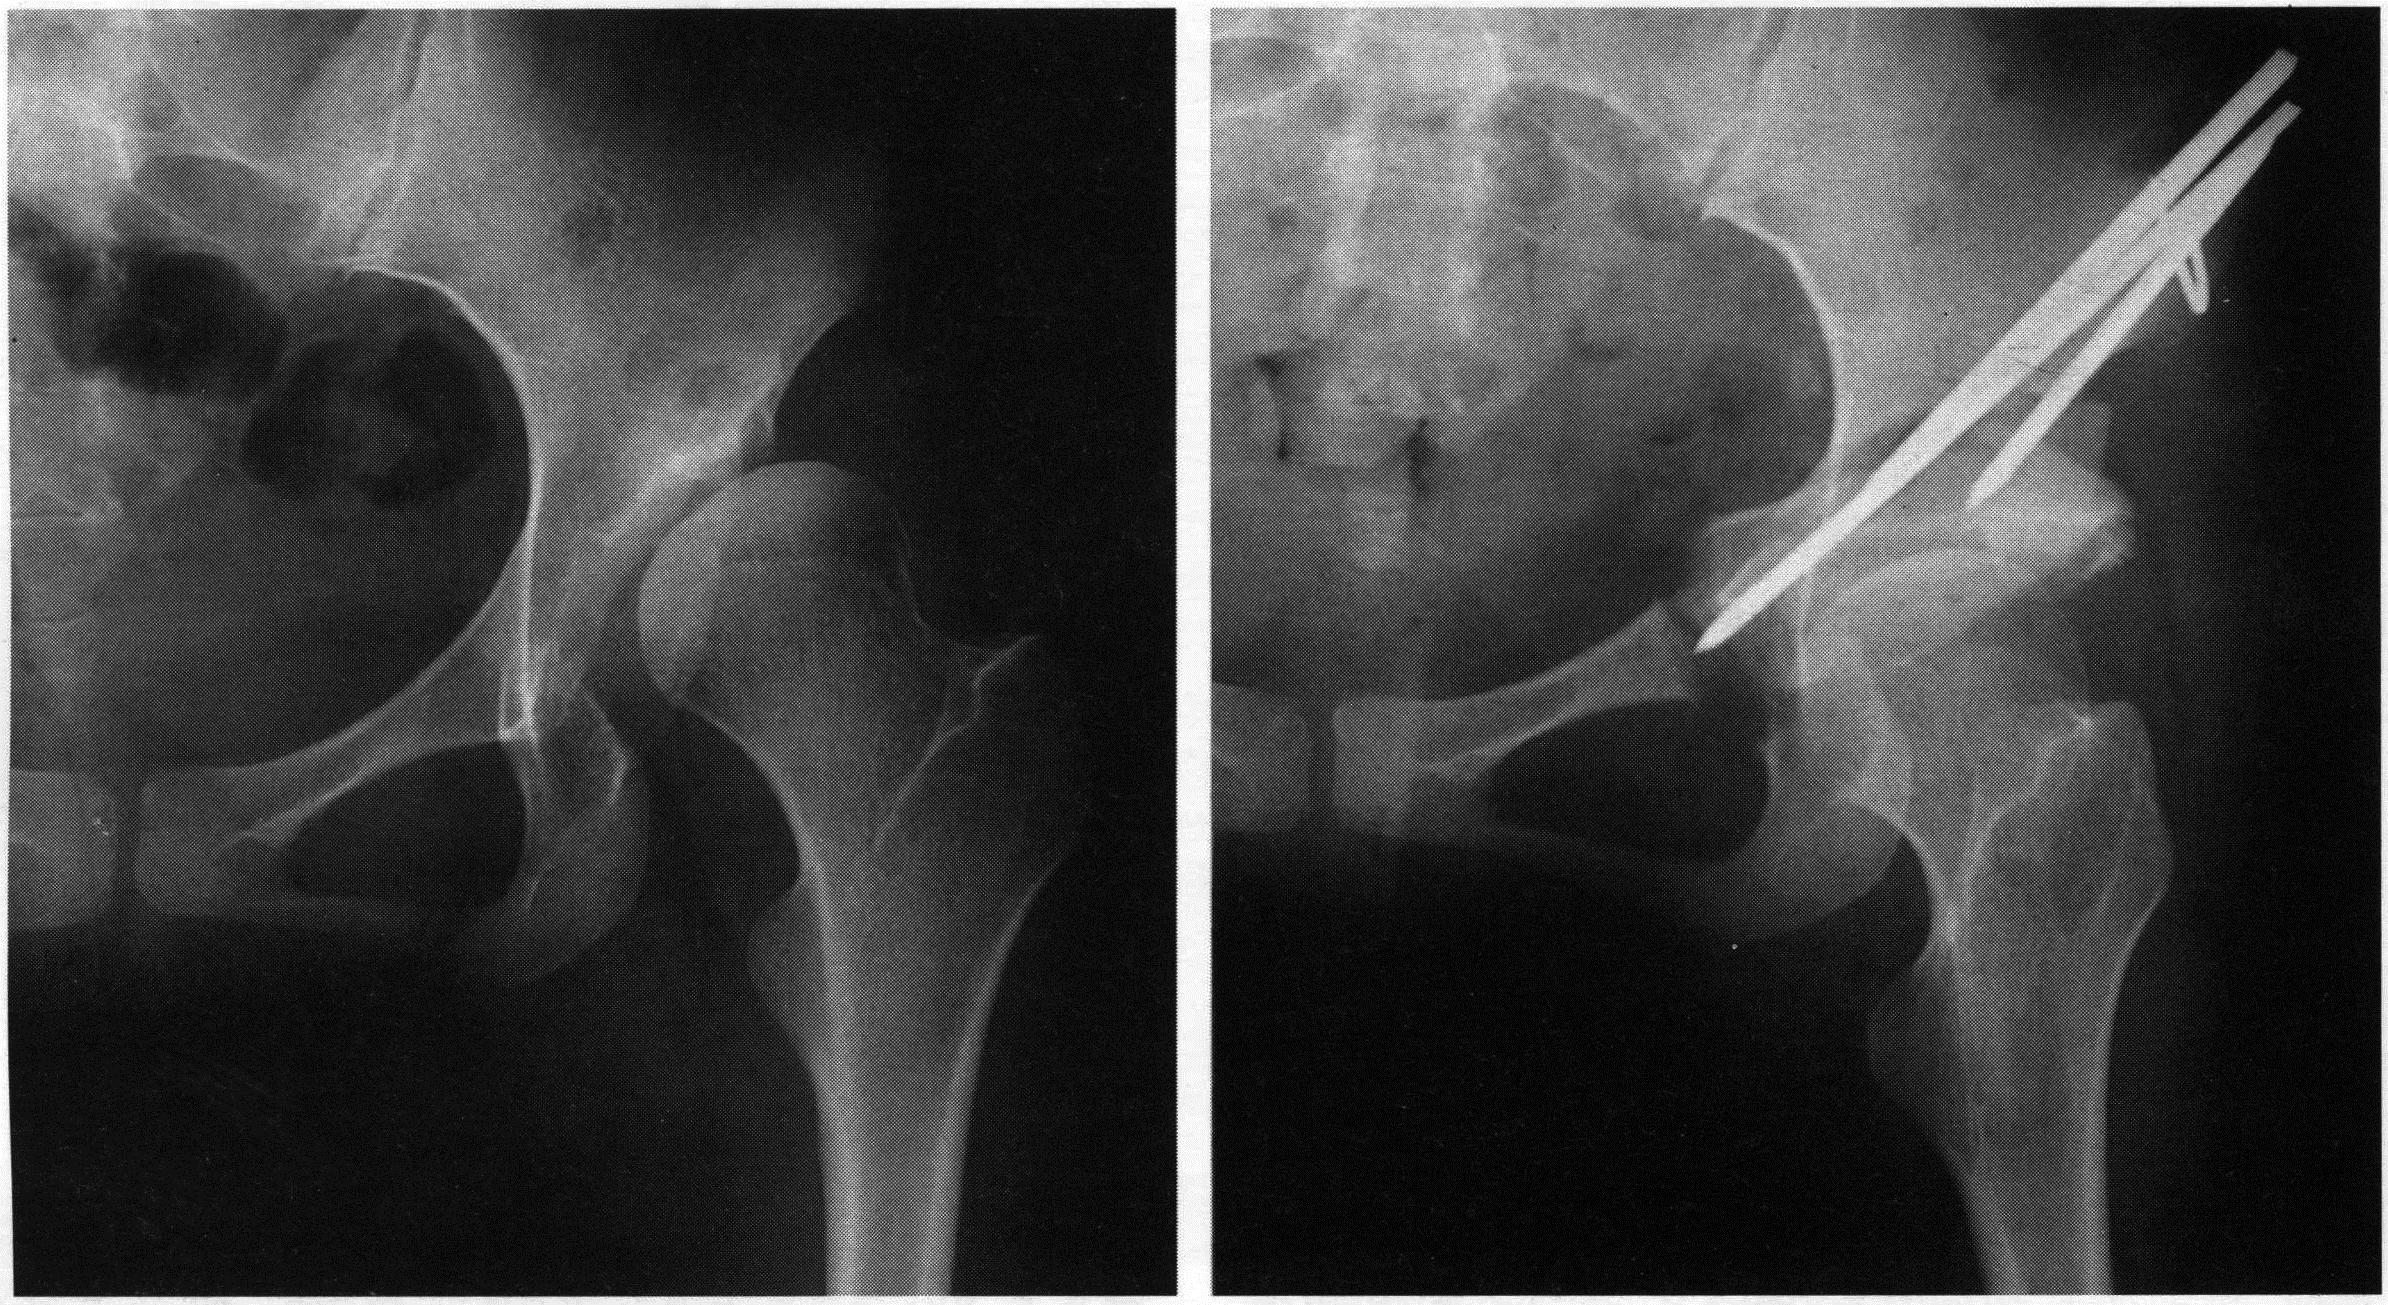

영상 진단: X-레이, MRI 또는 CT 스캔을 통해 수술 계획을 세웁니다.

절단과 재배열: 고관절의 뼈를 절단하고, 필요한 경우 뼈의 방향을 변경합니다.

고정: 절단된 뼈 조각을 금속 핀, 나사, 또는 판으로 고정합니다.